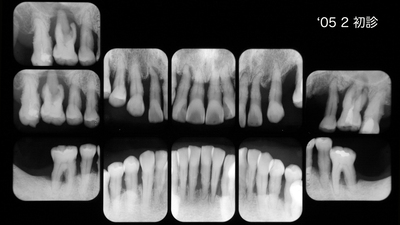

初診時30代男性。「歯並びを治したい」が主訴でしたがプロービングデプス全顎8〜9mmの重度歯周炎でした。歯周治療後全顎pd2~3mmに改善を確認、矯正治療は専門医山田秀樹先生にお願いしました。

矯正治療が終わりました、といわれても上顎犬歯遠心にスペースを残す、やや控えめな歯牙移動、、、それが私の眼には物足りなく思ったものでした。しかし経過を観察すること初診から5年、骨レベルは安定し歯肉はタイトに引き締まってプローブははいらないばかりか付着歯肉が増大してきました。良好な経過から矯正専門医の適切で妥当な判断だったといえます。さすがです。

メンテナンスに移行

急発〜挺出〜咬合性外傷 で上顎前歯は抜けそうでしたが、なんとか助かりました。右上1右下2近心のX-P像に注目ください。動的治療期間2年弱ですからまあまあでしょう。